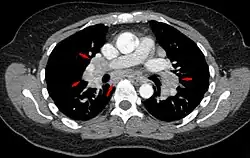

CT scan of the chest showing lymphadenopathy (arrows) in the mediastinum due to sarcoidosis

Diagnosis of sarcoidosis is a matter of exclusion, as there is no specific test for the condition other than the Kveim-Siltzbach test. To exclude sarcoidosis in a case presenting with pulmonary symptoms might involve a chest radiograph, CT scan of chest, PET scan, CT-guided biopsy, mediastinoscopy, open lung biopsy, bronchoscopy with biopsy, endobronchial ultrasound, and endoscopic ultrasound with fine-needle aspiration of mediastinal lymph nodes (EBUS FNA). Tissue from biopsy of lymph nodes is subjected to both flow cytometry to rule out cancer and special stains (acid fast bacilli stain and Gömöri methenamine silver stain) to rule out microorganisms and fungi.[99][100][12][101]